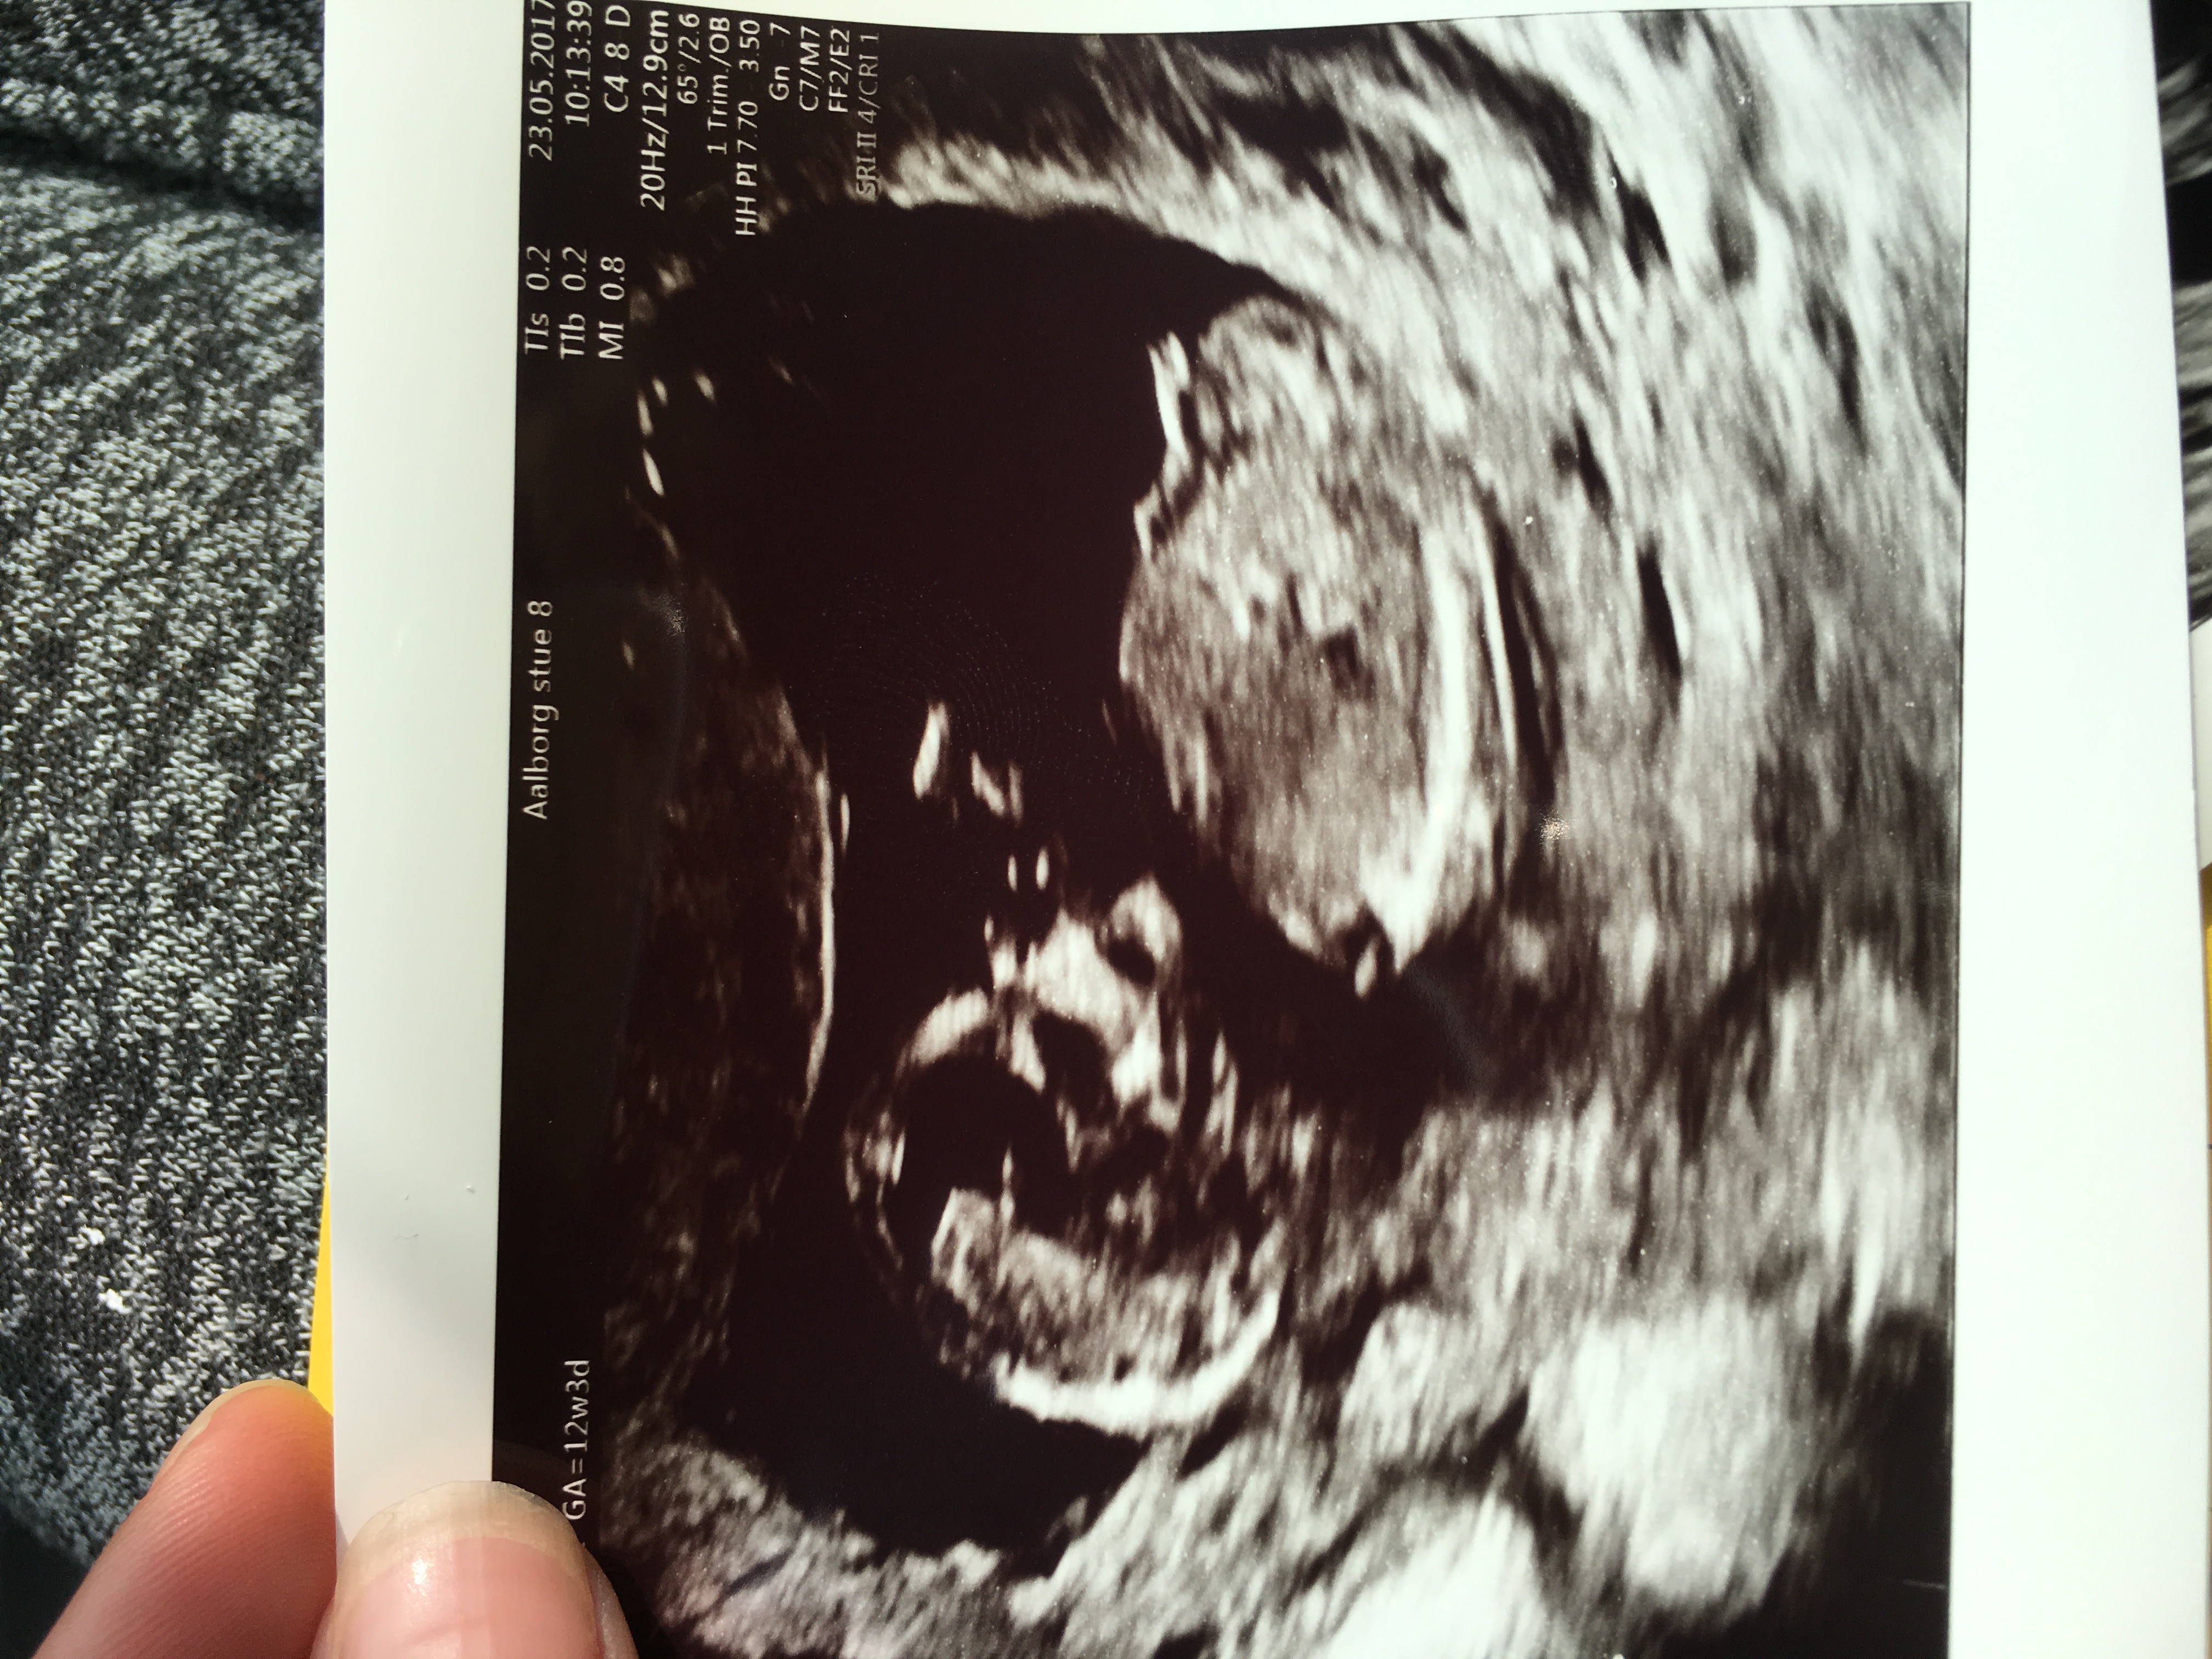

Girl or boy? I'm not sure .. anyone who will guess